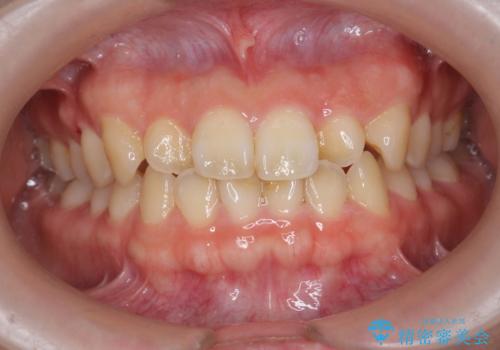

- 「前歯のねじれ、見た目を改善したい。」と矯正治療を希望され来院されました。

マウスピース矯正では改善の難しい前歯のねじれを前歯の部分ワイヤー矯正で改善したのち、インビザライン矯正を行い歯列を整えます。